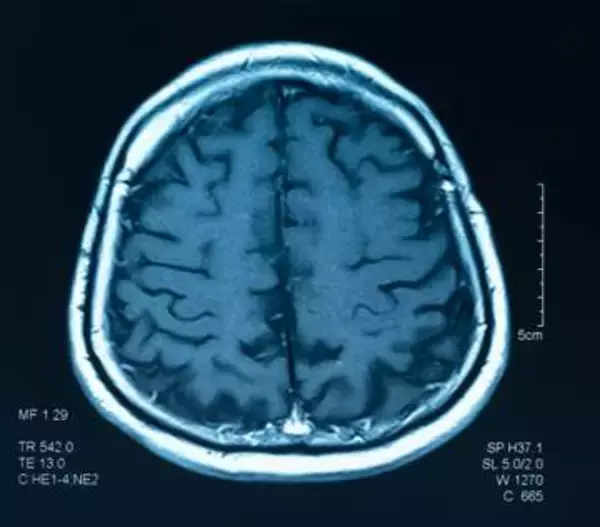

目覚ましい進歩を続けるAI(人工知能)。人が見たり聞いたりしたものを、AIが脳から再現する研究がいま...